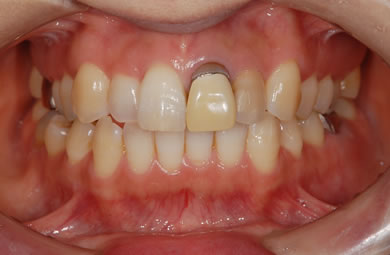

インプラントの症例写真 IMPLANT

インプラント治療+セラミック治療

| 主訴 | 前歯を白くしたい。 | ||||||||||||||||||||||||||||||||

| 治療方針 | 前歯部の審美的回復をセラミック治療で行う。臼歯部の審美的・機能的回復をインプラント治療で行う。 | ||||||||||||||||||||||||||||||||

| 治療内容 | インプラント1本、メタルボンドセラミック1本、オールセラミック2本(オールセラミック用の土台2本) | ||||||||||||||||||||||||||||||||